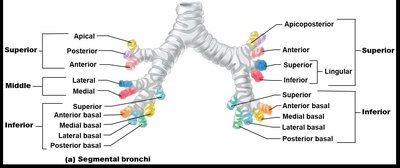

The trachea is a flexible tube supported by C-shaped cartilage rings, leading to the primary bronchi, which branch into secondary (lobar) and tertiary (segmental) bronchi, and finally into bronchioles and terminal bronchioles.

Bronchi: Right lung has three secondary bronchi, left lung has two; further branching forms the bronchial tree.

Bronchopulmonary Segments: Functionally independent units of the lung.